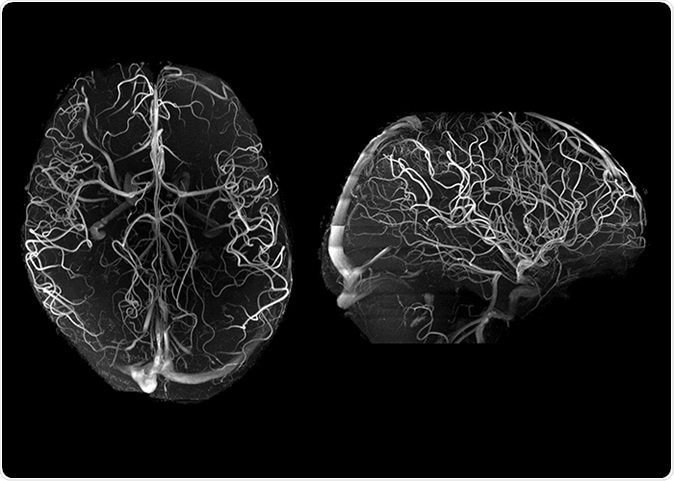

7T angiography in late life depression patients with the “Tic-Tac-Toe” RF coil system and without the use of invasive contrast agents. While not feasible at 3T, 7T super high-resolution acquisitions (voxel size is 0.2 mm in all directions) significantly improve the conspicuity of small arterioles.

This imaging tool is one of only about 60 in the whole world and has been used to study human anatomy as well as to conduct experiments. At 7T MRI, arterioles in the brain become conspicuous, enabling the study of small vessel disease.